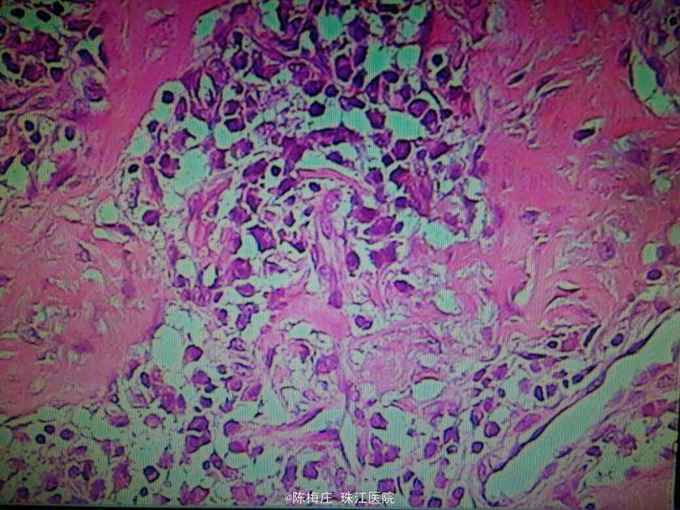

诊断:腹部切口愈合不良;剖宫产术后。 予行腹部切口二期缝合术。予术中予常规消毒铺单,于腹部切口右侧窦道口处切开皮肤一周,向下完整切除窦道,深达筋膜层,切面新鲜,电凝止血,用双氧水、生理盐水、灭滴灵依次冲洗切口,4号丝线间断全层缝合皮下及皮肤。术后病理(如图):腹部慢性炎伴异物多核巨细胞反应。